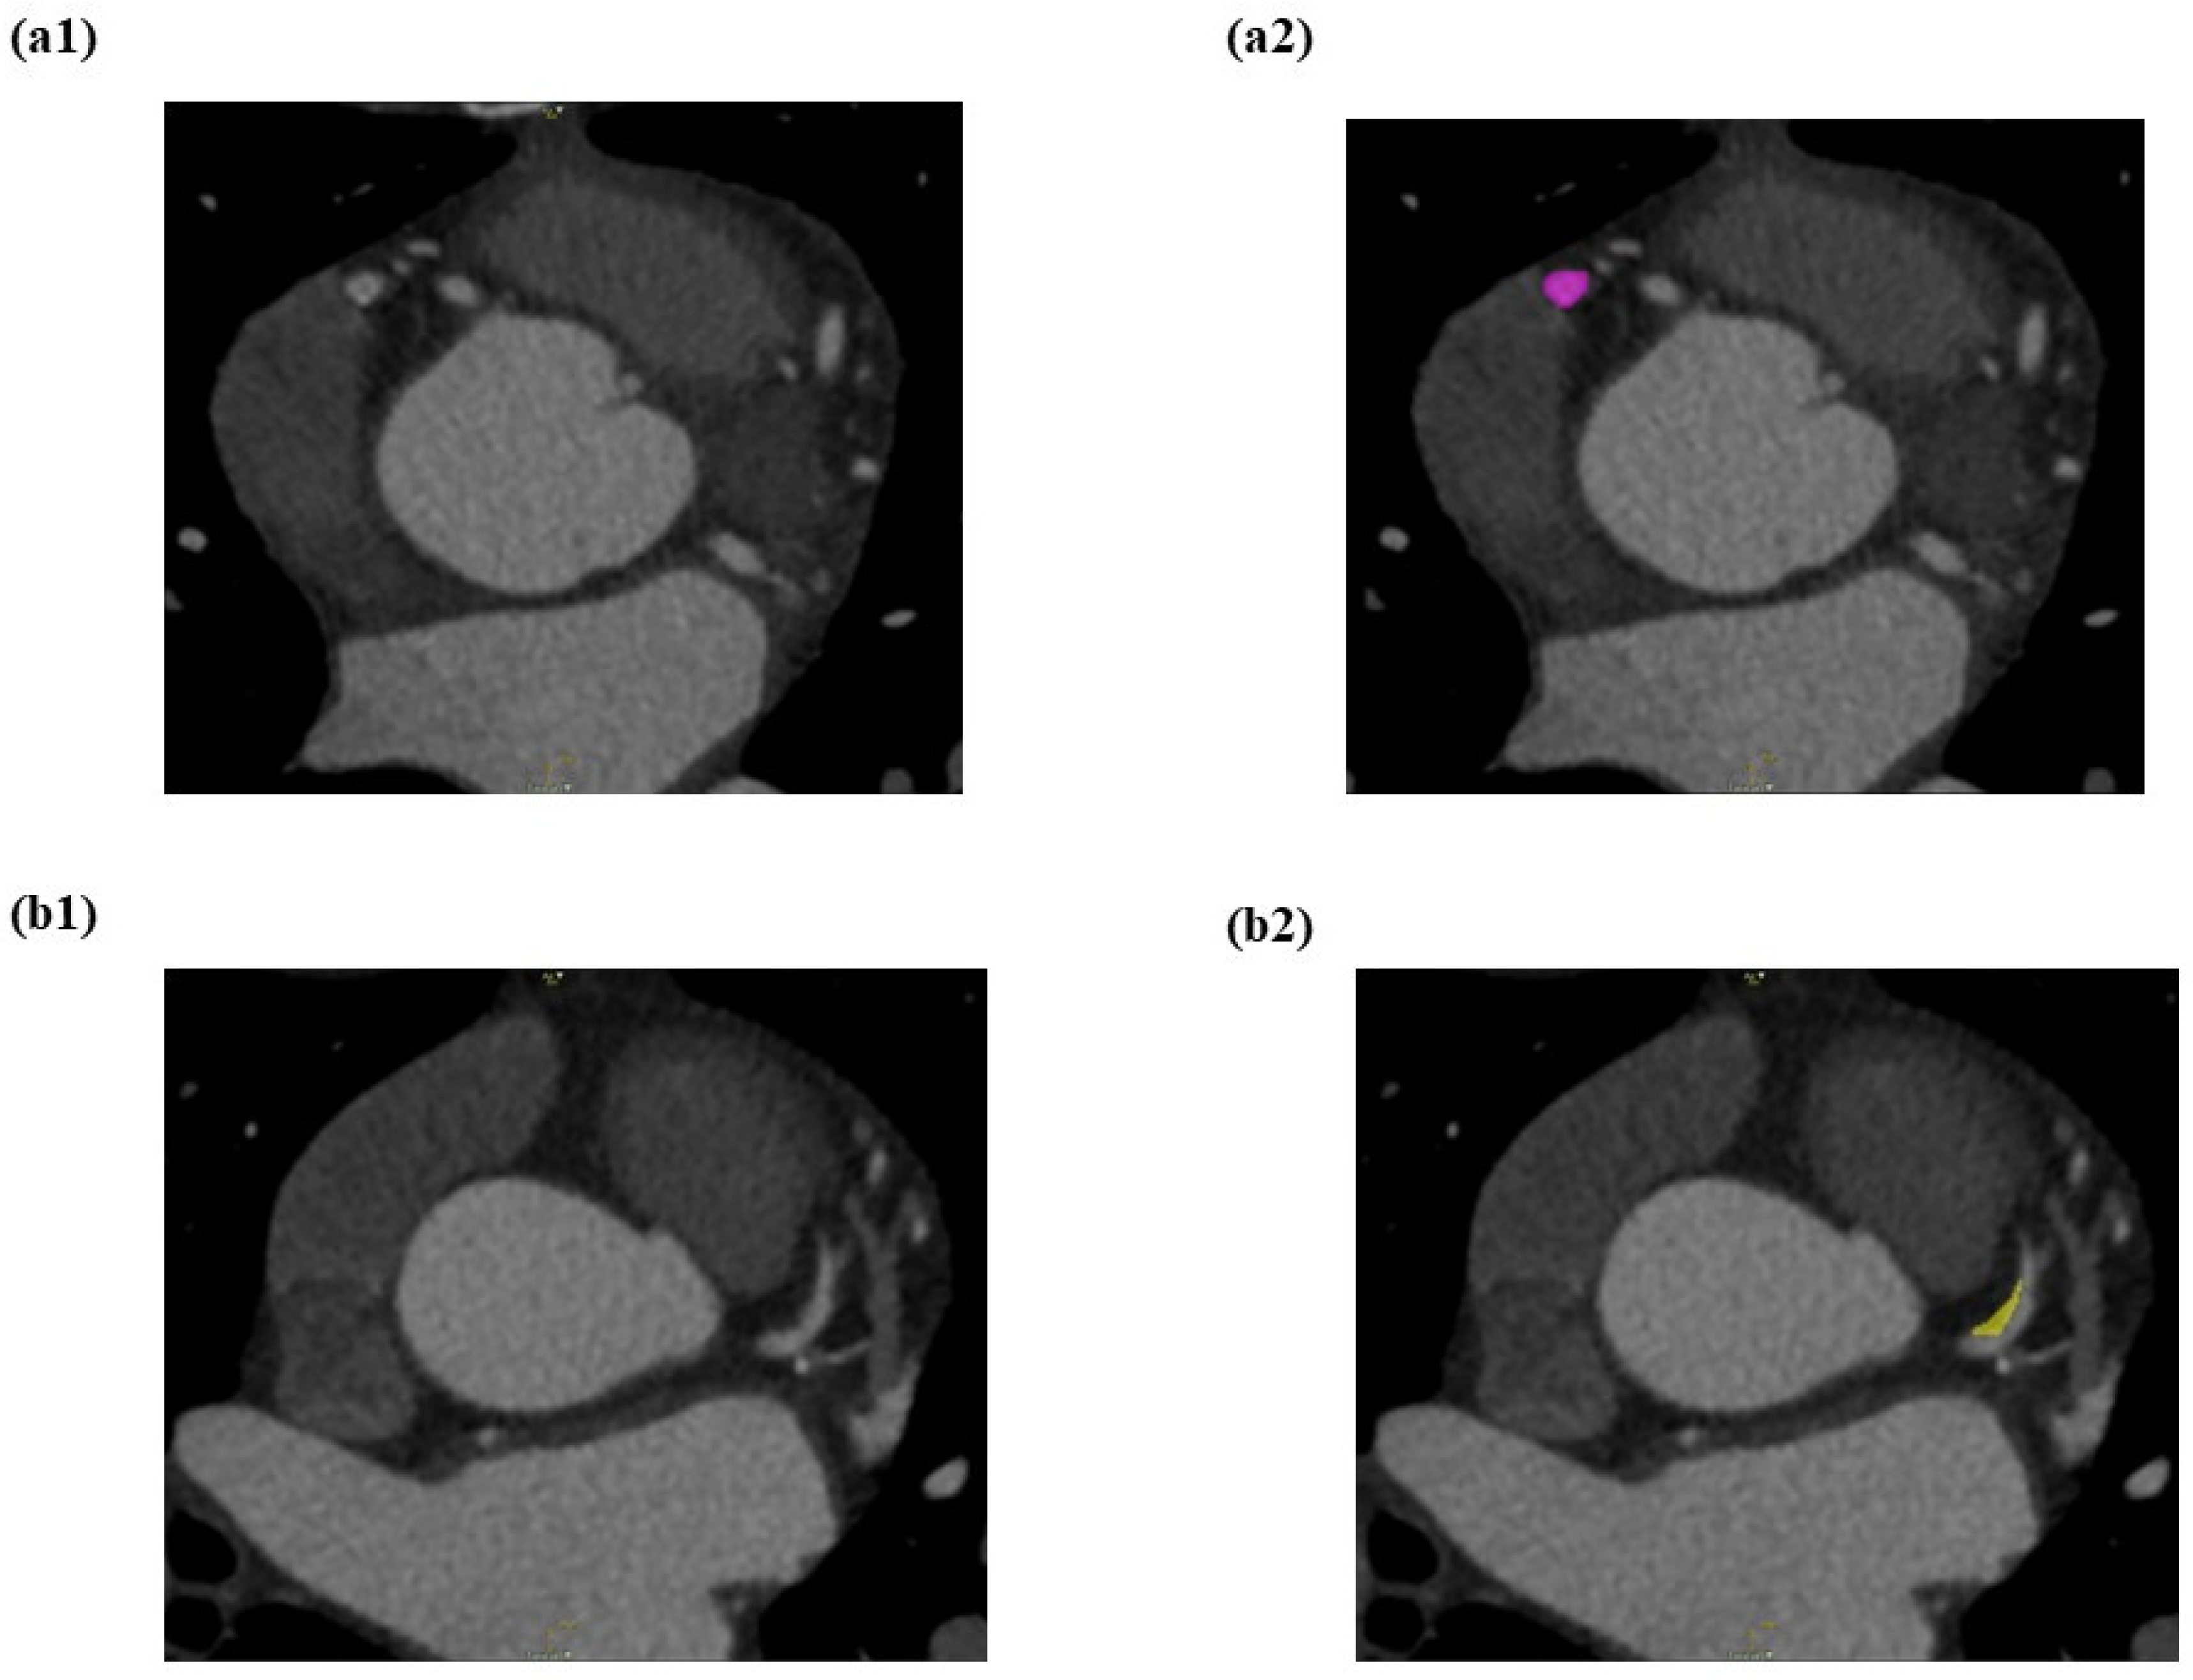

The LIFEx (7.0.16 version) programme was used to semi-automate the segmentation of all CCTA pictures. The RCA, LAD, and LCX are the three primary coronary arteries that were segmented. For each image, a 3D brush (a semi-automatic segmentation technique) was used to draw the volume of interest (VOI) on the spesific identified vessels. As a first step, the reader marks the area of interest. In the second step, semi-automated segmentation done on the next slice and repeat again to the next slice. Then, the LIFEx software will automatically tries to establish the next slice of segmentation area based on luminal intensity values by growth from seed approach. The segmentation area is subsequently presented to the reader for manual correction. Figure 4 showed the CCTA images of the pre-segmentation and the post-segmentation process on non-calcified lesions on proximal LAD.

Figure 4.

(a) Before segmentation of proximal LAD and (b) after segmentation of non-calcified lesion on proximal LAD using semi-automated (growth from seed) type of segmentation which was colored into yellow colour.

In this study, the proximal, mid, or distal parts of the RCA, LAD, and LCX where regardless the plaque is present or not is segmentized. The segmentation of the normal coronary artery was identified as a control group. Three adjacent slices of the area of interest were used to segment the VOIs, which were then stored in the system. The segmentation was verified by an independent observer, a senior cardiologist at IJN. A detailed explanation of the segmentation method was shown in Figure 5.

Figure 5.

LIFEx software is used to perform semi-automated segmentation on RCA, LAD, and LCX. (a1) Mid RCA with a mixed calcified atherosclerotic plaque seen. (a2) The mixed calcified plaque was enclosed by the VOI placement (pink colour) on the mid RCA. (b1) Proximal LAD with a non-calcified atherosclerotic plaque was seen. (b2) The non-calcified plaque was surrounded by the VOI placement (yellow colour) on the proximal LAD. (c1) Proximal LCX with a calcified atherosclerotic plaque was observed. (c2) The calcified atherosclerotic plaque was surrounded by the VOI placement (blue colour) on the proximal LCX.